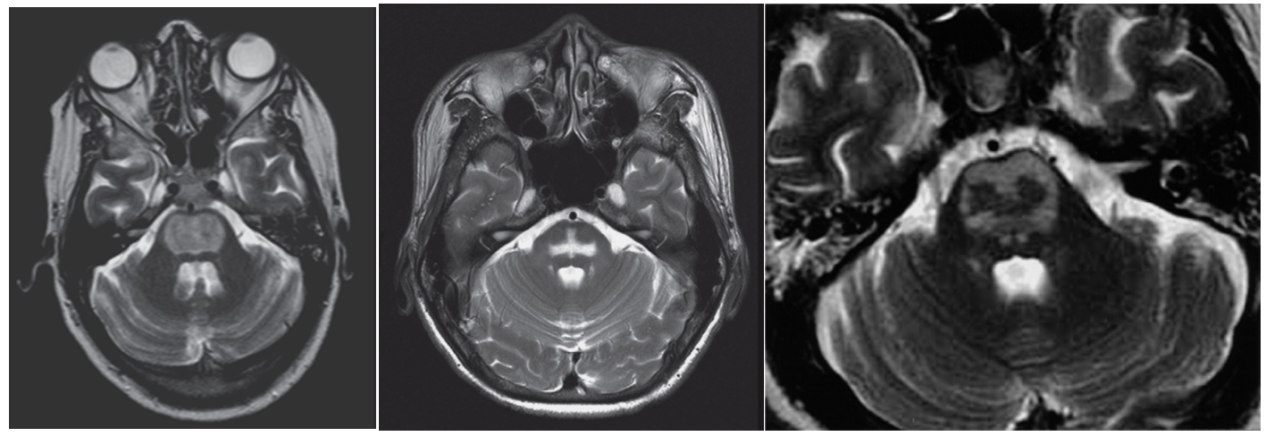

三、桥脑中央髓鞘溶解症(central pontine myelinolysis, CPM)

这是渗透性脱髓鞘综合征的一种类型,常见于快速纠正低钠血症及慢性酒精中毒患者。CPM是脑桥基底部的急性髓鞘溶解性病变,组织病理学上是一种非炎症性脱髓鞘,而神经元和相关轴突相对保留,伴少突胶质细胞数量减少和巨噬细胞浸润。

影像表现(MRI):桥脑基底部长T1、长T2信号,T2Flair高信号,其形态可呈“蝙蝠翅”征、“三叉戟”征或“猪鼻”征。

四、桥脑外髓鞘溶解症(extrapontine myelinolysis, EPM)

此为中枢髓鞘溶解症的一种临床类型,以脑桥之外的髓鞘溶解为特点,是一种临床少见疾病,对其缺乏充分的认识。诱导发生脑桥外髓鞘溶解症的危险因素除低钠血症(血钠<136mmol·L-1)外,酒精滥用、肝肾功能衰竭、营养不良等均可为其诱因。病变可广泛累及基底节区、丘脑、大脑皮质及皮质下白质等部位,其临床表现与影像学表现均缺乏特异性。